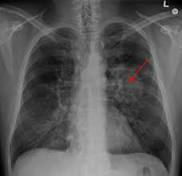

Although clinical trials have shown that lung cancer screening using low-dose computed tomography (LDCT) can detect lung cancers early and ...

Younger patients – aged 50 to 64 – are more likely to be diagnosed with late stage lung cancer than older patients according to new data* being ...